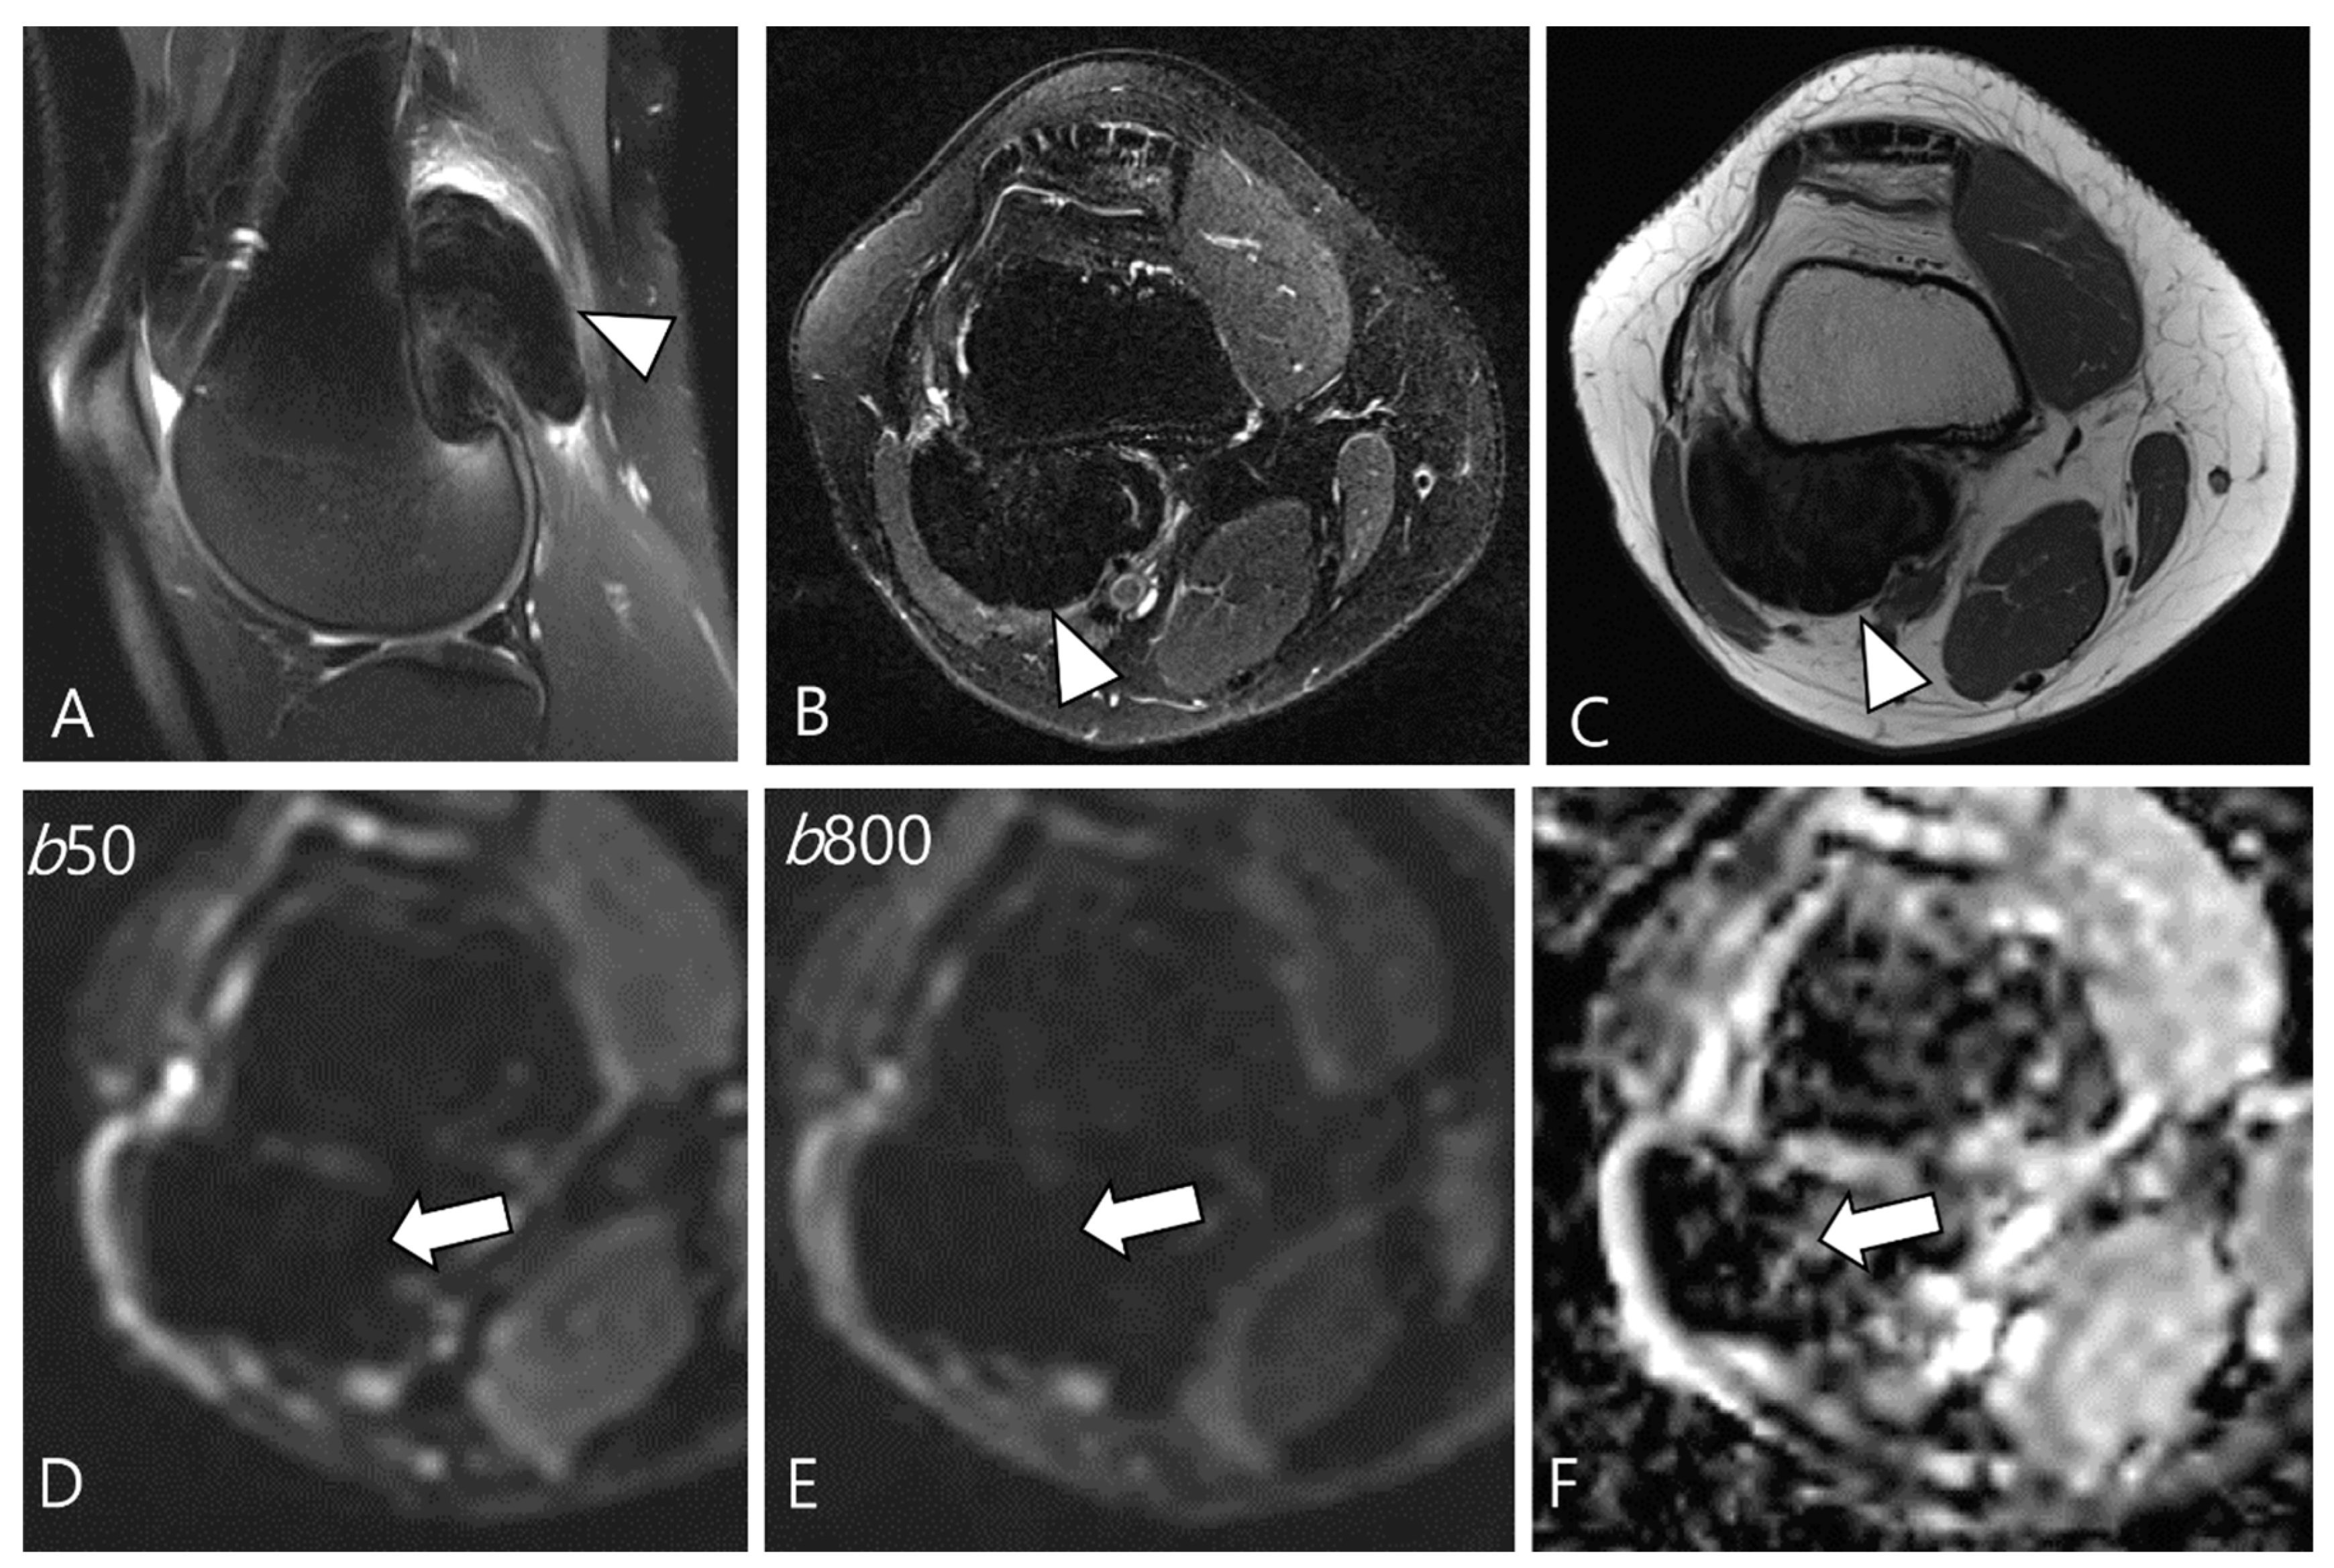

2.5. Advanced MRI Sequences for D-TSGCT